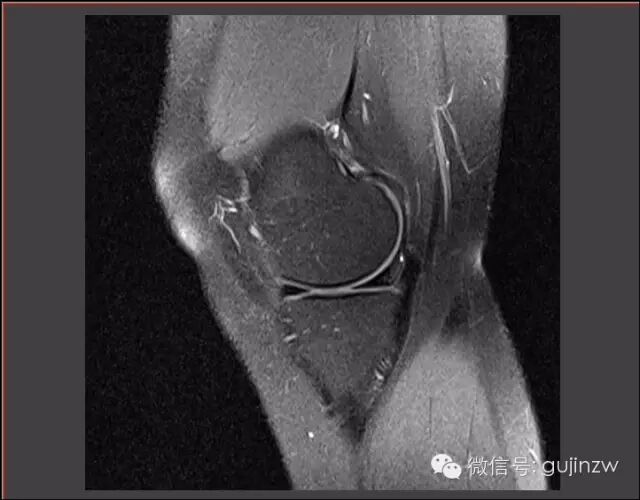

病例3

• 男,25岁。

• 主诉:打篮球扭伤致右膝关节疼痛半年。

• 症状:轻微跛行,右膝关节疼痛,活动时有不稳感,无交锁、打软腿。

• 体征:膝关节活动度:0-135度,浮髌试验弱阴性,内外侧关节间隙无压痛。

• 被动挤压:麦氏征(-),Apley征(-)。

• 主动挤压:Ege‘s征(-),Thessaly  20°征(+)。